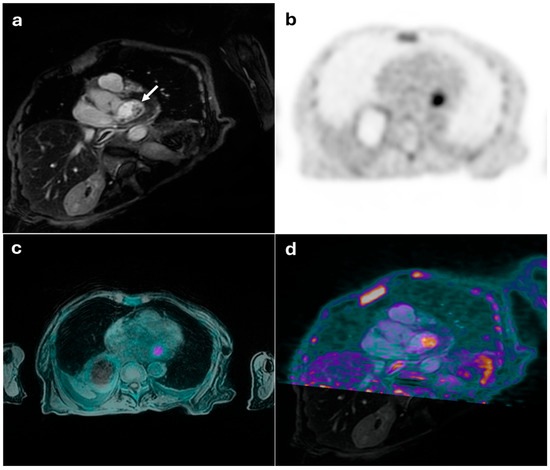

Figure 4.

55-year-old male with suspected myopericarditis. (a) displays an MRI image showing a linear myo-epicardial late gadolinium enhancement in the mid-basal inferolateral wall of the left ventricle, suggestive of non-ischemic pattern fibrosis, possibly indicative of prior myocarditis. (b,c) show PET images with no distinct areas of radiotracer uptake in the myocardial walls, consistent with a negative result. The combined PET/MRI findings were conclusive for non-active myocarditis of the left ventricle (d).